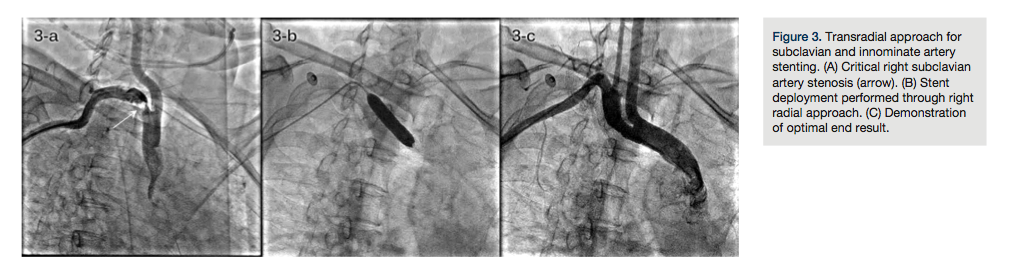

TRA for carotid artery stenting. Carotid artery stenting is an accepted treatment modality as an alternative to carotid endarterectomy for revascularization of atherosclerotic internal carotid artery stenosis in patients who are at high risk for surgery.14,15 Traditionally, the femoral approach is utilized with acceptable success rates. Small feasibility studies using ipsilateral and contralateral TRA have been published.14,15,32,49

The 5Fr Simmons-1 catheter (Terumo) is a workhorse catheter to cannulate the common carotid artery using both ipsilateral and contralateral TRA. For contralateral TRA, the 5Fr Tig-1 Optitorque catheter (Terumo) is an alternative catheter.

A .035-inch Amplatz super-stiff wire is parked in the external carotid artery or deep in the common carotid artery away from the origin of the internal carotid artery.

Aim at optimal co-axial positioning of a 6Fr or 7Fr carotid sheath of your choice in the common carotid artery (Figure 4A).

The remaining steps of the procedures are the same as with TFA (Figures 4B and 4C).